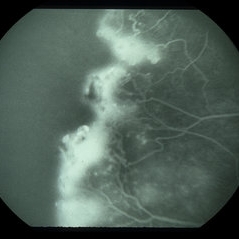

Sickle cell retinopathy (Proliferative) (2 files)

Sickle cell retinopathy (Proliferative) (2 files)

Proliferative sickle retinopathy (1 file)

Proliferative sickle retinopathy (1 file)

Proliferative Sickle Cell Retinopathy (Stage3) (10 files)

Proliferative Sickle Cell Retinopathy (Stage3) (10 files)

Sickle Cell Retinopathy (11 files)

Sickle Cell Retinopathy (11 files)

Sickle Cell Retinopathy SC (6 files)

Sickle Cell Retinopathy SC (6 files)

Sickle Cell (1 file)